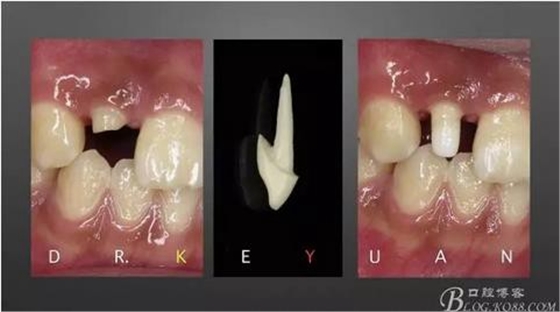

5、制作臨時(shí)冠(邊緣很關(guān)鍵,不要對(duì)齦緣造成壓迫)

6、有時(shí)候除了工作更有生活,讓自己和顧客靜下來喝杯茶

(雖然顧客很著急恢復(fù)自己的笑容,我們也很著急,臨床中常常因?yàn)橹弊詈蟮貌坏胶芾硐氲男Ч?,讓我追悔莫及,如果這次治療能換來以后時(shí)光里的長久穩(wěn)定的修復(fù)效果,這點(diǎn)時(shí)間也值得,最近有很多病例的不完善讓我深刻認(rèn)識(shí)到術(shù)中不努力、術(shù)后徒傷悲,寫在這里讓自己謹(jǐn)記,每一個(gè)環(huán)節(jié)都不能偷懶)

7、最終爭取了2周的時(shí)間,能看到牙齦有明顯的改善